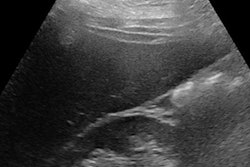

LiverMultiScan images of patient with fatty liver disease before (above) and after (below) bariatric surgery. Based on these scans, it was decided liver biopsy was not needed in this patient. Copyright Perspectum Diagnostics.The study, conducted by researchers at the University of Birmingham and the University of Edinburgh, investigated the performance and cost of multiparametric MRI (LiverMultiScan) alongside existing biomarkers in the assessment of nonalcoholic fatty liver disease (NAFLD). Adult patients undergoing standard-of-care liver biopsy for NAFLD were prospectively recruited at the two U.K. liver centers in Birmingham and Edinburgh, and they underwent multiparametric MRI, blood sampling, and transient elastography within two weeks of liver biopsy. The researchers compared noninvasive markers, with histology as the gold standard.

They found LiverMultiScan in 50 patients and six healthy volunteers was superior for grading disease severity and excluding people at increased risk of disease progression, compared with the other tests evaluated.